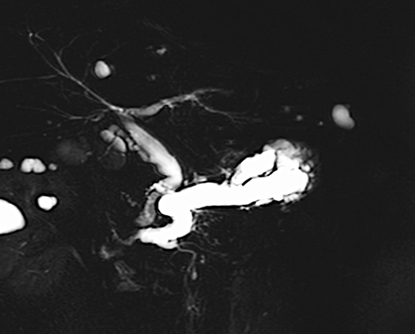

術後の良性胆管空腸吻合部狭窄に対する胆道ドレナージと拡張術

(十二指腸癌で膵頭十二指腸切除術、Child再建後)

膵頭十二指腸切除後に胆管空腸吻合部の狭窄を認めた症例です。

手術後1年が経過した頃に肝胆道系酵素の上昇を指摘され、内視鏡治療を行いました。胆管空腸吻合部に良性の狭窄を認めたため、狭窄部に対して金属ステントを交差するように留置しました。ステントは2~3か月程度留置した後に抜去することで、吻合部の狭窄は改善しました。

内視鏡治療後は肝胆道系酵素も改善し、その後は吻合部狭窄の再発も認めていません。